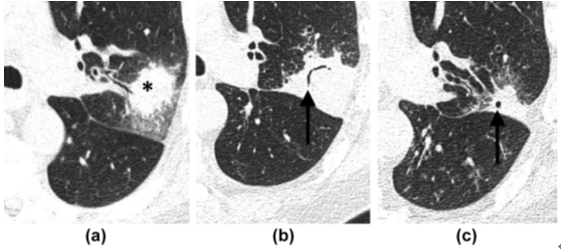

4. 侵袭性肺曲菌病主要发生在免疫功能严重受损的患者,常伴中性粒细胞减少。局部肺动脉被菌丝堵塞,曲霉菌对血管有特殊的亲和力,侵犯血管导致血栓形成,造成小的梗死灶,梗死灶周围的出血和渗出形成CT上边缘模糊的磨玻璃影,称“晕征”。约1~3周后,随着中性粒细胞水平恢复正常,感染区会形成空洞,出现“空气新月征”(图6),此征象是由梗死的肺组织回缩牵拉空洞壁造成的,也被认为是预后良好的表现。

图 6 急性白血病骨髓移植术后患者,中性粒细胞减少。(a)左肺上叶局部实变(*),伴周围磨玻璃样晕环。(b)恢复期可见“空气新月征”(箭头)。(c)残留的瘢痕和小空洞(箭头)。痰培养证实为烟曲菌感染。